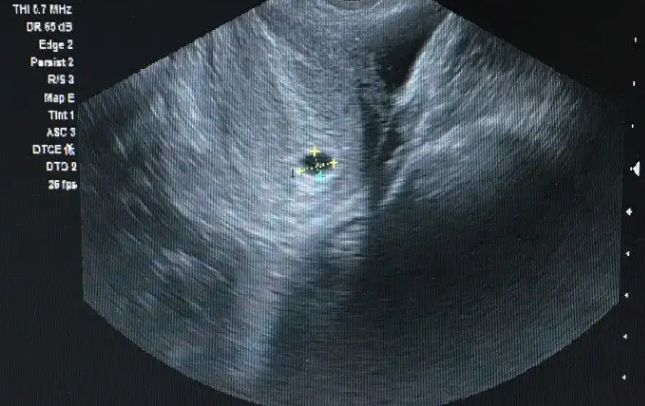

全麻真香!长海医院麻醉评估超快,睡5分钟取16颗卵(隔壁姐妹无麻也说像蚂蚁夹)